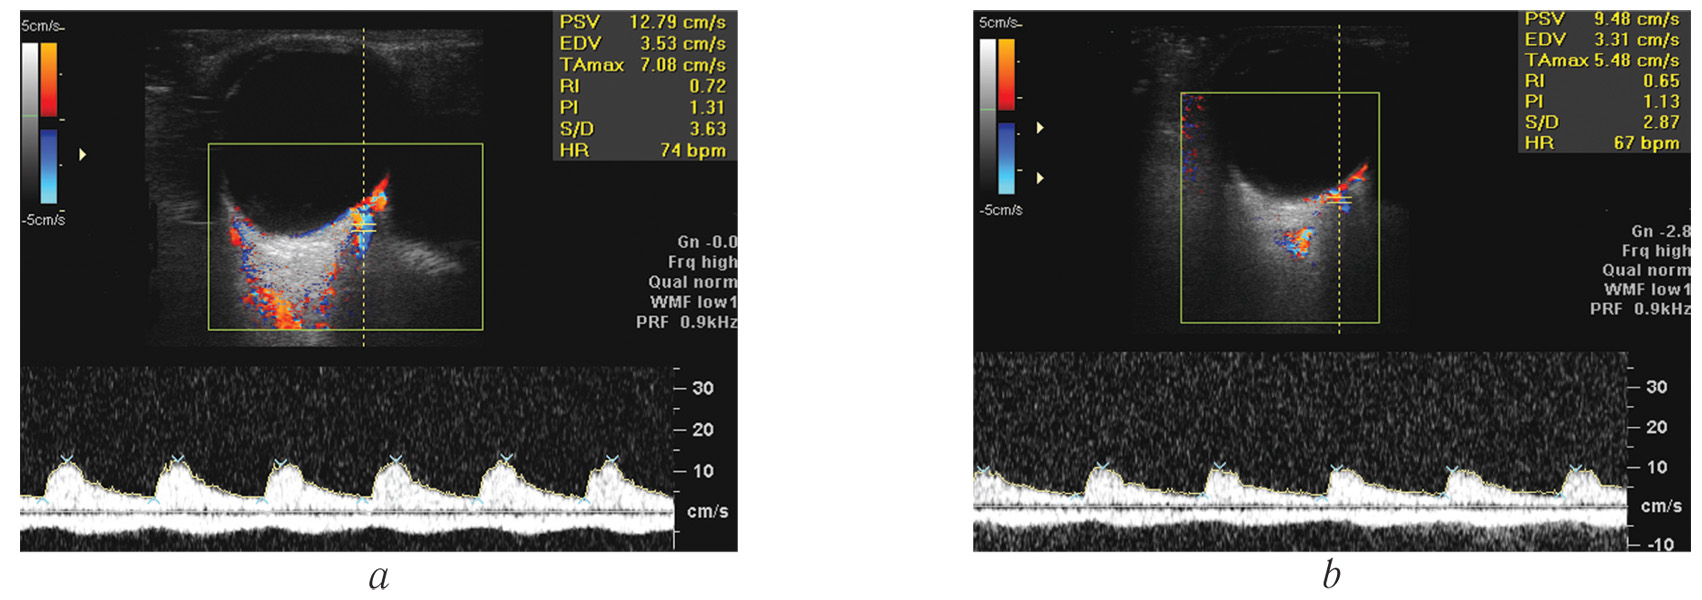

In the operating room, the ocular blood flow was studied 3 times: immediately before surgery, immediately after sealing the operative access at a given intraoperative level of IOP (Fig. 1, a and b), and after normalization of the IOP and resealing of the corneal tunnel (Fig. 2). The interval between the second and third measurements averaged 3.48 ± 0.36 hours. Blood flow was determined in retrobulbar vessels, namely the central retinal artery (CRA) and the central retinal vein (CRV), with registration of the maximum systolic blood flow velocity (Vsyst), final diastolic blood flow velocity (Vdiast), and resistance index (RI).

Fig. 1. The Doppler spectral analysis of blood flow velocities in the central retinal artery: a – before cataract surgery (Vsyst = 12.3 cm/s, Vdiast = 4.1 cm/s); b – immediately following cataract surgery (Vsyst = 9.4 cm/s, Vdiast = 3.3 cm/s)

Рис. 1. Доплеровский спектр кровотока в центральной артерии и центральной вене сетчатки: a — непосредственно перед операцией (Vsyst = 12,3 см/c, Vdiast = 4,1 см/c); b — сразу после операции (Vsyst = 9,4 см/c, Vdiast = 3,3 см/c)